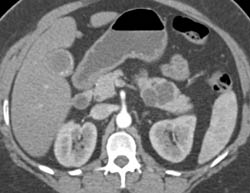

Diagnosis

Intraductal Papillary Mucinous Neoplasm (IPMN)